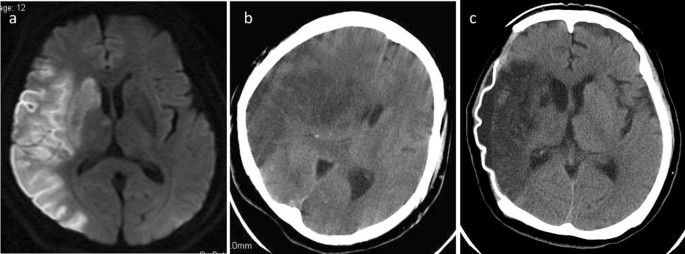

1. 신속한 평가 및 진단: 뇌경색 초기증상과 징후를 신속하게 인식하는 것은 적시에 개입하고 환자 결과를 개선하는 데 필수적입니다. 의료 전문가는 NIHSS(National Institutes of Health Stroke Scale)와 같은 도구를 사용하여 잠재적인 뇌경색 환자를 신속하게 평가하고 컴퓨터 단층 촬영(CT) 스캔 또는 자기 공명 영상(MRI)을 포함한 진단 테스트를 시작하여 진단을 확인하고 유형을 결정해야 합니다.